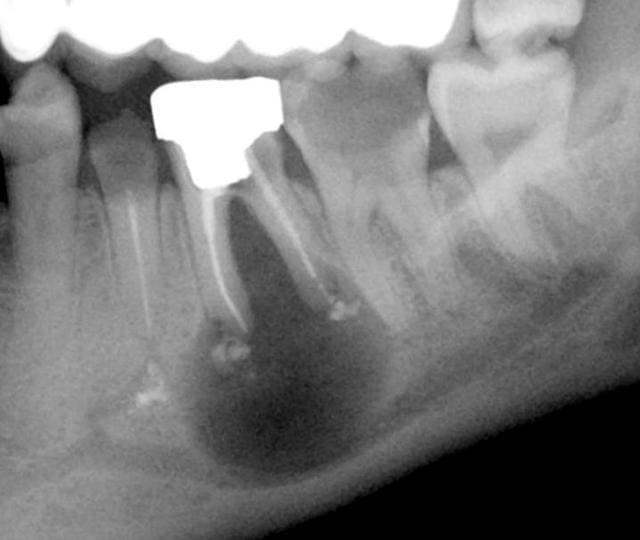

une precision, la 15 semble etre un pilier carié pas avoir été laissée en jachere...enfin, moi ce que j'en dis...

> une precision, la 15 semble etre un pilier carié pas avoir été laissée en

> jachere...enfin, moi ce que j'en dis...

Très probable en fait : mea culpa, c'est si facile de critiquer, pas toujours sain...

Jolie lésion, non ?

> Jolie lésion, non ?

C'est sensible ? non ? bon, on surveille cela, ça va sûrement se placer tout seul...

Ah, la p'tite bulle qui coule sur le côté...

Le plancher n'a pas l'air top...